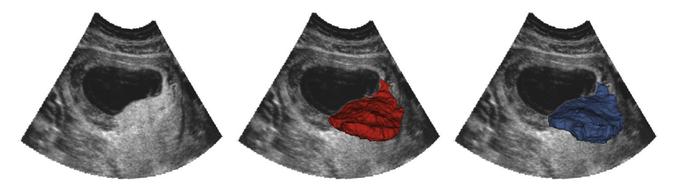

Figure 3

OxNNet compared to groundtruth.

Placental segmentations with 2D B-mode plane (left). RW segmentation (center; red). OxNNet prediction (right; blue). The values of the Dice similarity coefficient and Hausdorff distance metrics for this case were 0.838 and 12.6 mm, respectively.